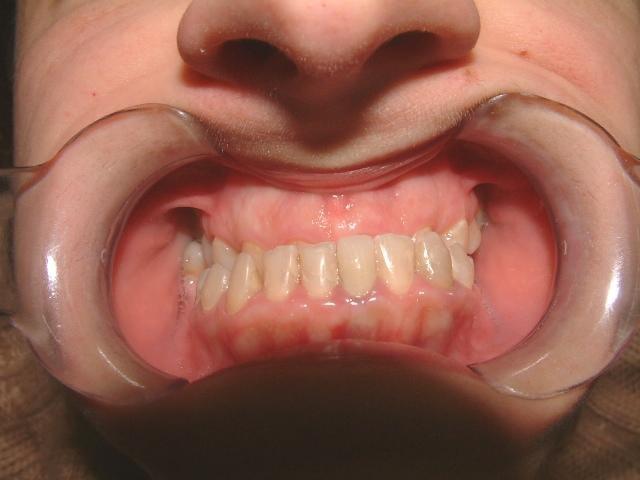

1η περίπτωση

Αρχική οδοντοσκελετική κατάσταση παιδιού με προγναθισμό άνω γνάθου και έντονη οριζόντια πρόταξη άνω τομέων Η σημασία της στοματικής υγιεινής και ορθοδοντικής

027 Αμέσως μετά το τέλος της ορθοδοντικής θεραπείας. Οι αλλαγές στην οδοντική του σύγκλειση αλλά και στο πρόσωπο είναι εμφανείς 15 χρόνια μετά την αρχική περάτωση της θεραπείας, το αποτέλεσμα παραμένει σταθερό και ο ασθενής απέκτησε ένα υγιές και αρμονικό χαμόγελο και πρόσωπο. Η σημασία της στοματικής υγιεινής και ορθοδοντικής πρόληψης